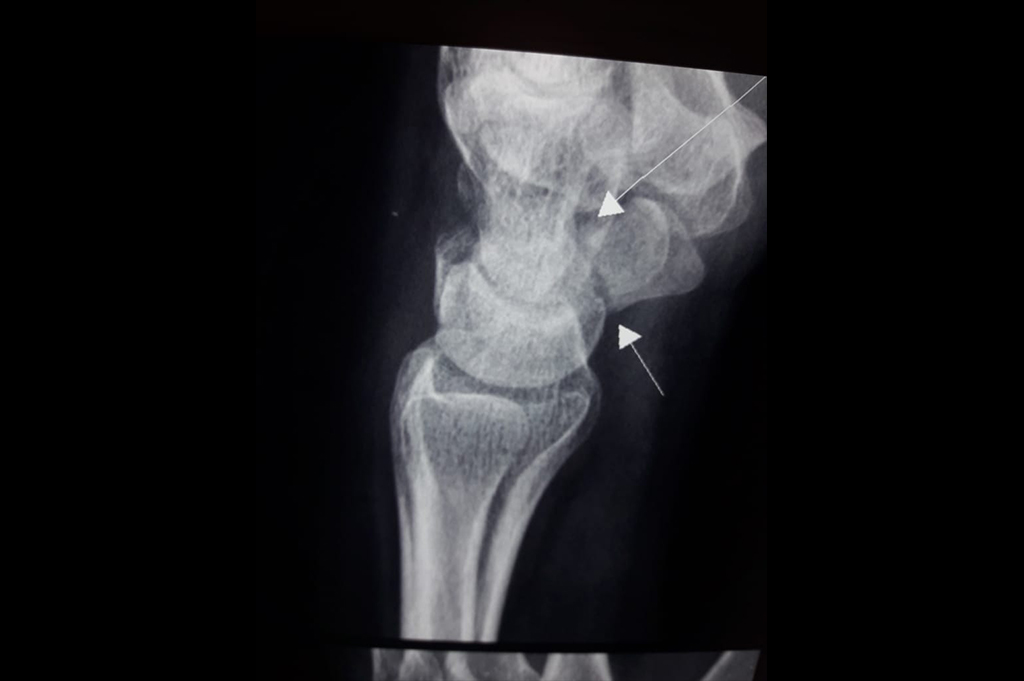

Elbow